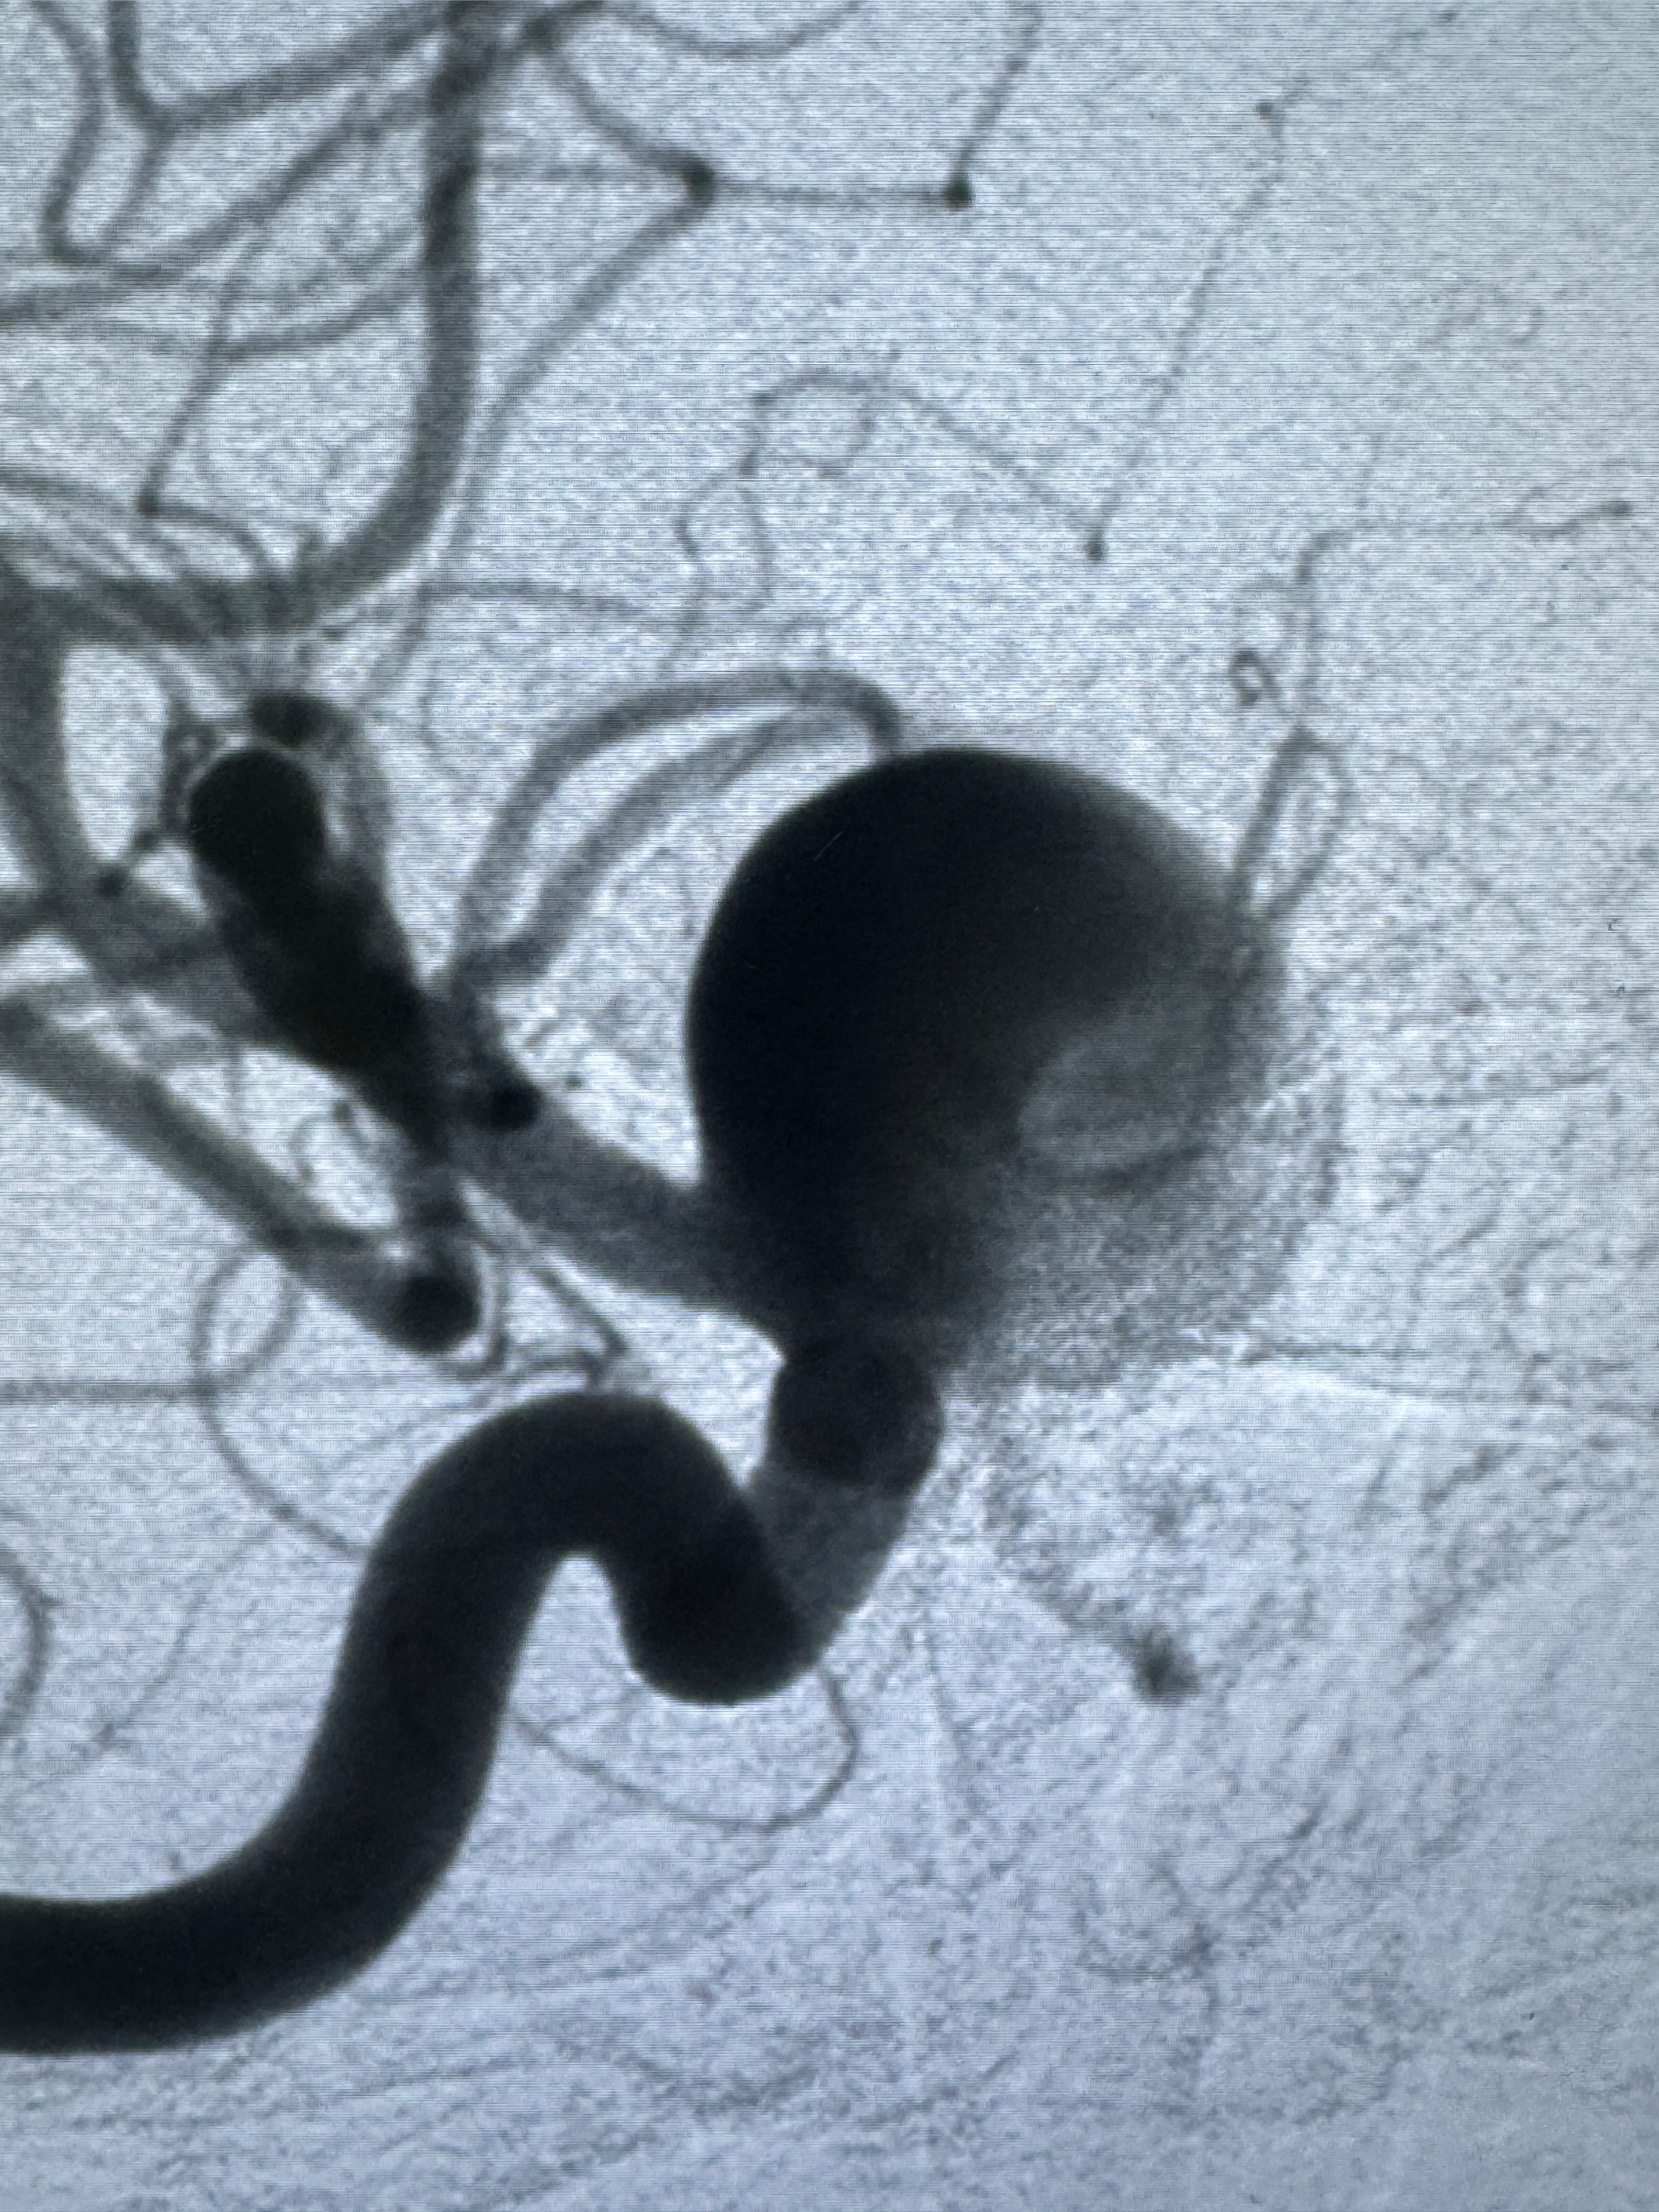

2023-12-08 复旦大学附属华山医院 全脑血管造影:右侧颈内动脉C6段动脉瘤,瘤颈6.68mm,动脉瘤大小13.28*12.34mm

2023-12-08外院DSA:右侧颈眼动脉瘤,约13*12mm大小,压颈试验显示左右向及后向前代偿可

测量动脉瘤的大小:16*13.8*7.6mm大小,较原先变大,考虑双抗后瘤内血栓溶解可能